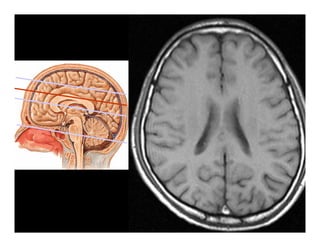

Giải phẫu

Tổn thương